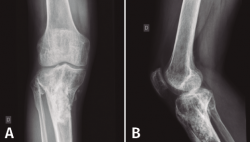

En el estudio radiológico (Figura 2) se objetiva fractura consolidada de la tibia con amplia desestructuración ósea.

Figura 2. Radiografías de frente y de perfil de tibia-peroné donde se objetiva fractura consolidada con amplia desestructuración ósea.